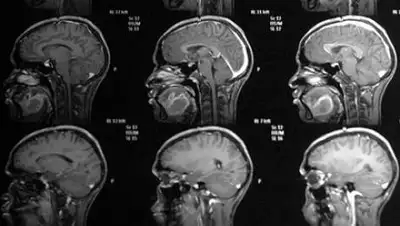

Онколог назвал первые признаки рака головного мозга

Как пояснил врач, рак мозга может быть нескольких типов: первичный — развивающийся непосредственно в тканях головного мозга, а также вторичный, являющийся метастазой опухоли из другого органа. При этом заболевание сложно распознать на первых этапах. Дело в том, что в основном оно развивается бессимптомно.